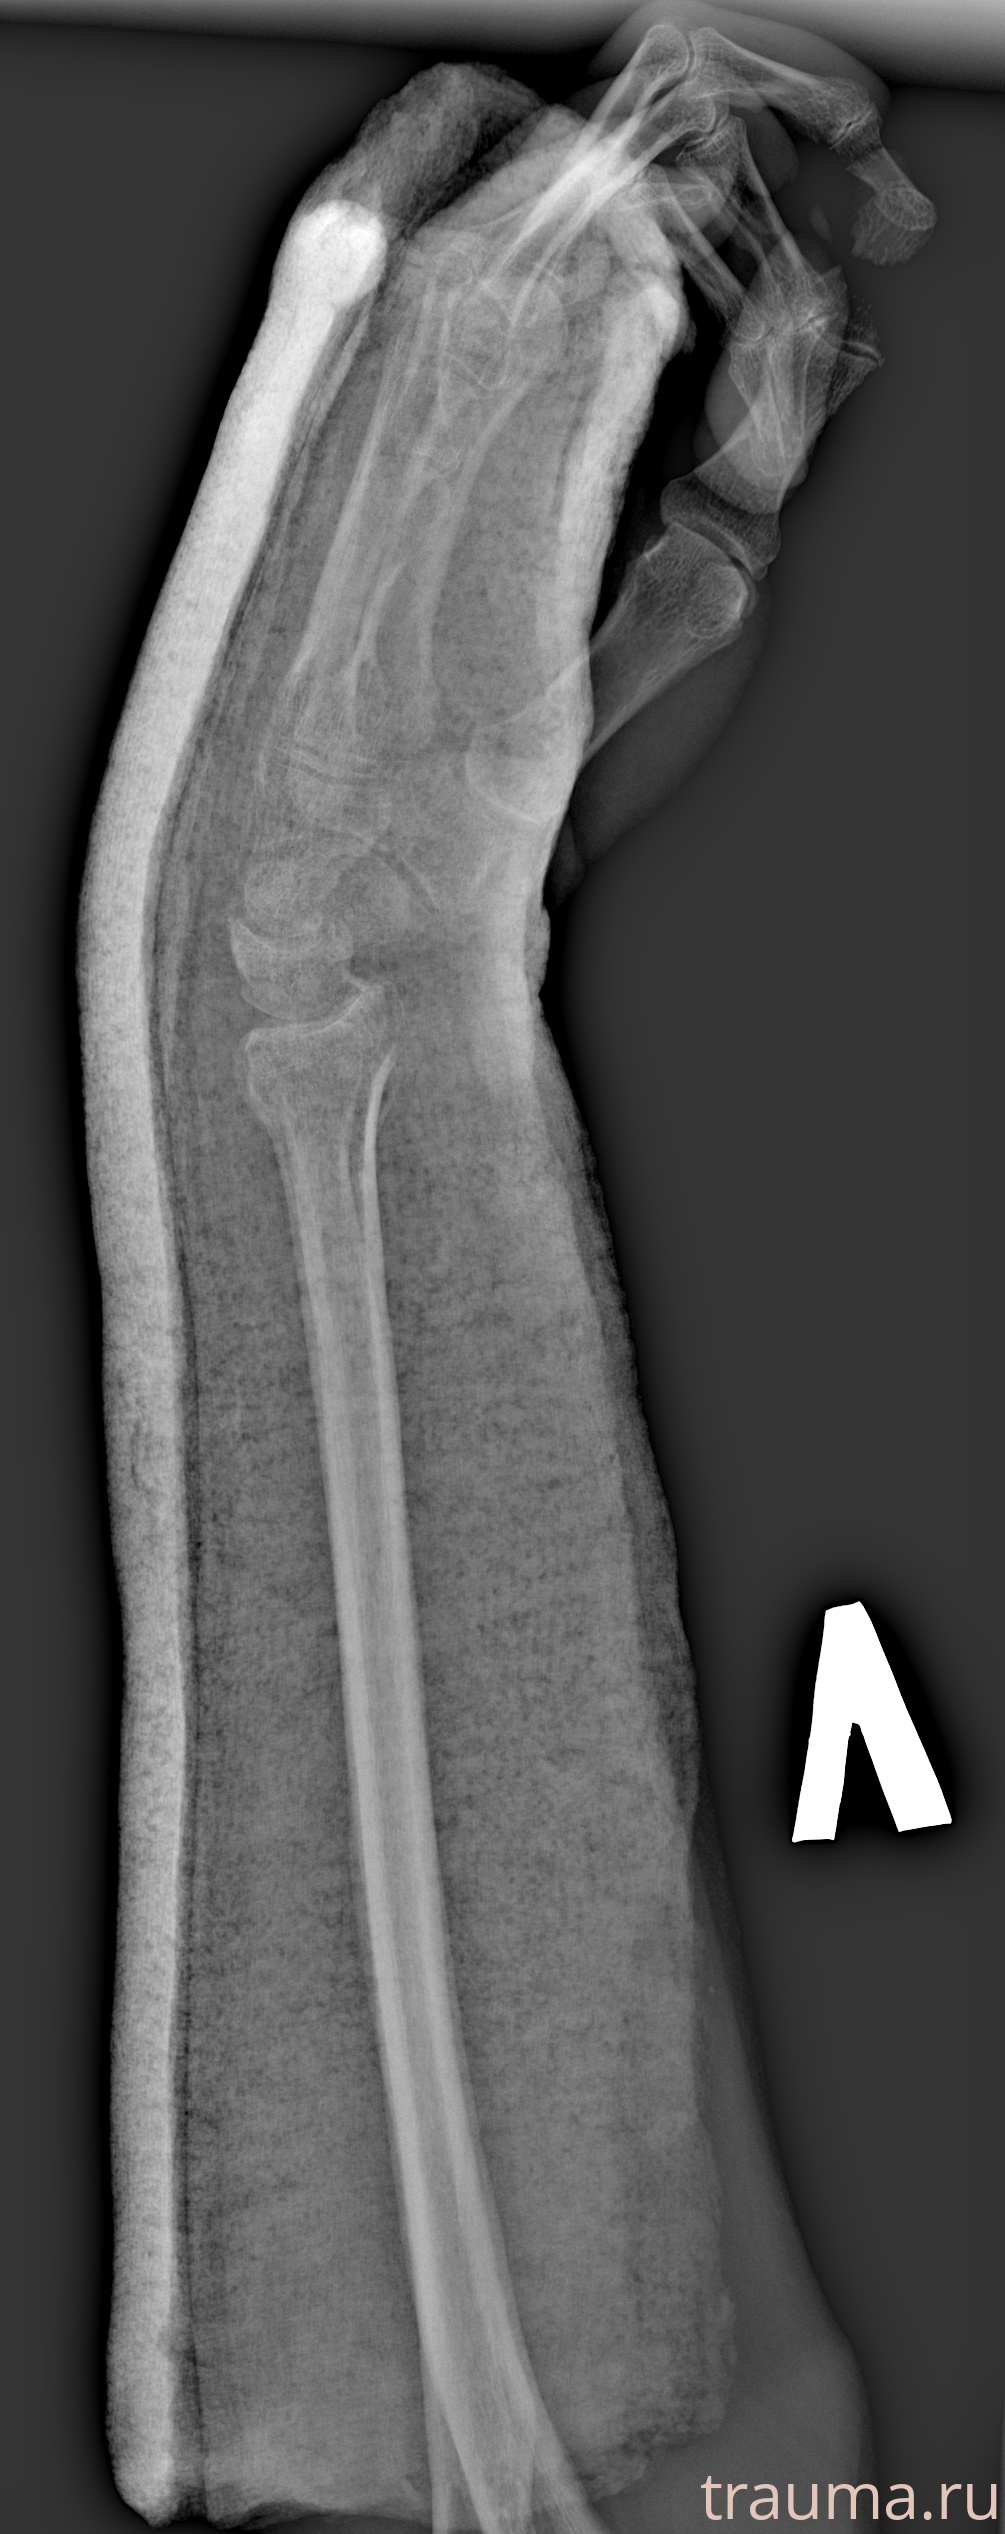

Рентгенограммы

Рентген на дому: по вашему адресу приезжает врач-рентгенолог, травматолог-ортопед с мобильным рентгеновским аппаратом, проводит диагностику травмы или заболевания, делает необходимые рентгенограммы, дает рекомендации по дальнейшему лечению. Получить качественные снимки в домашних условиях возможно благодаря уникальной методике, разработанной МосРентген Центром для института  Склифосовского